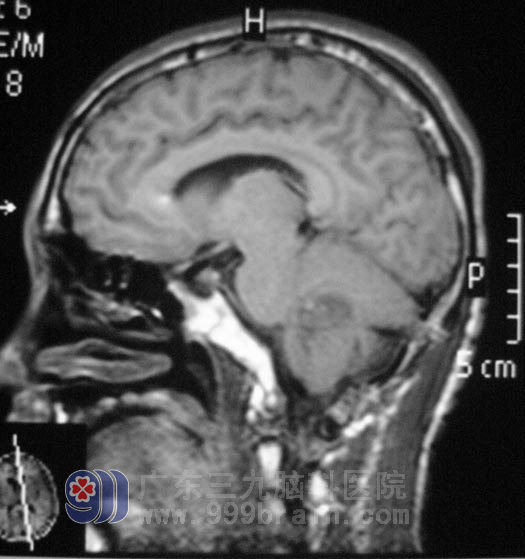

17岁的小昭,一直是健康活泼,只在入院的前一周出现头晕,伴头痛、呕吐,精神食欲差,体重下降,当地医院检查头颅CT提示:小脑占位;在广东三九脑科医院检查头颅MR提示四脑室占位伴梗阻性脑积水:http://www.999brain.com/

广东三九脑科医院综合神经外科鲁明主任告诉他们:肿瘤占位引起脑积水、颅内压力增高,引起头痛呕吐,占位效应明显,应尽早手术治疗,否则出现脑疝,后果非常严重。5月1日,鲁明主任为小昭在全麻下行右侧脑室外引流术+脑干四脑室占位切除术。显微镜下见灰白色肿瘤组织,质软,肿瘤血供丰富、包膜边界欠清晰,术中见肿瘤起源于右侧脑干背侧,充填四脑室,伸入四脑室侧孔。将肿瘤全切后,经过精心的治疗护理,小昭已经出院回家休养。术后病理检查结果为:髓母细胞瘤,WHO IV级。

髓母细胞瘤是中枢神经系统恶性程度最高的神经上皮性肿瘤之一,生长隐蔽,早期症状缺乏特征,常被病人亲属和医生所忽略,首发症状为头痛、呕吐等,多数患者因四脑室梗阻产生颅内压增高而出现呕吐,头痛症状加重才就诊。髓母细胞瘤一般多发生于学龄前或学龄期儿童尤其是男孩。http://www.999brain.com/